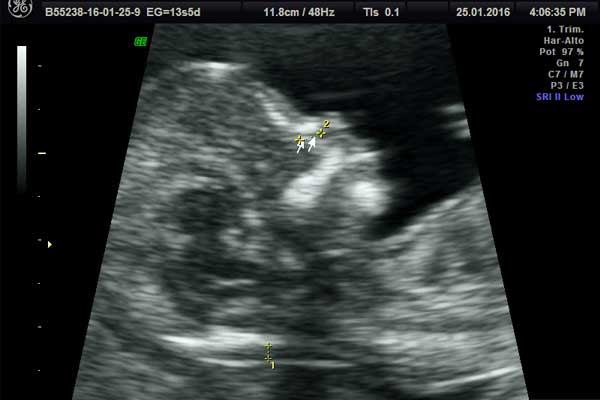

Translucencia nucal

El tamizaje genético es una prueba de detección precoz que ayuda a establecer si el bebé viene con problemas de tipo cromosómico.

Tamizaje Genéico

Tamizaje genético

calculo riesgo de enuploidias